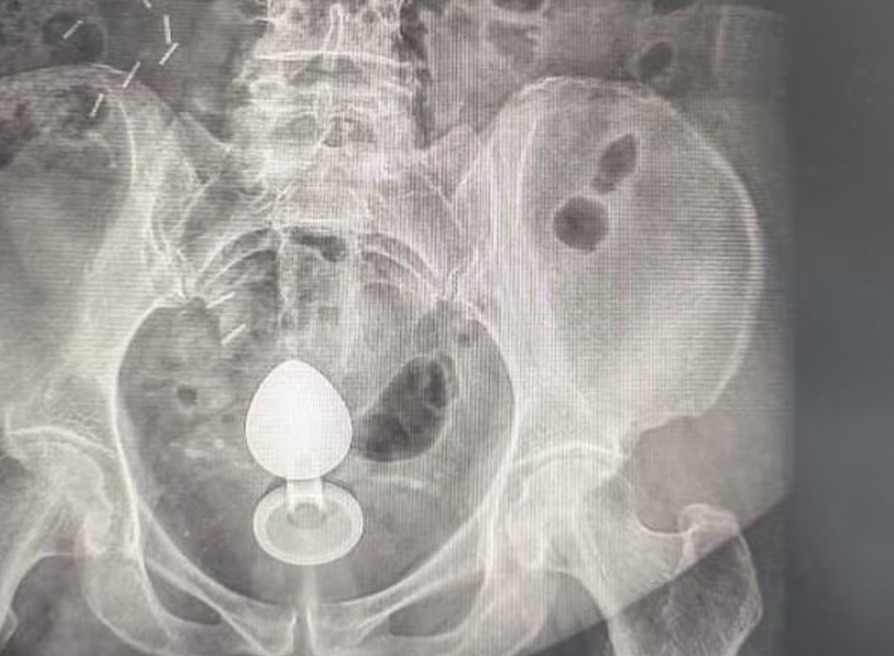

A paciente inseriu o plug anal por volta das 7h para tentar aliviar a constipação. Pouco mais de duas horas depois, ao sentar, percebeu que o objeto havia subido e não pôde ser retirado manualmente. Os movimentos peristálticos do intestino, responsáveis pelo funcionamento do órgão, podem ‘sugar’ objetos introduzidos nesta região. Em casos de condições médicas específicas, como pólipos intestinais, o risco de perfuração aumenta.

A paciente possuía pólipos no intestino, que são crescimentos anormais da mucosa com possibilidade de evoluir para câncer, tornando a parede intestinal mais sensível. O plug foi retirado por meio de procedimento médico e a mulher passa bem.